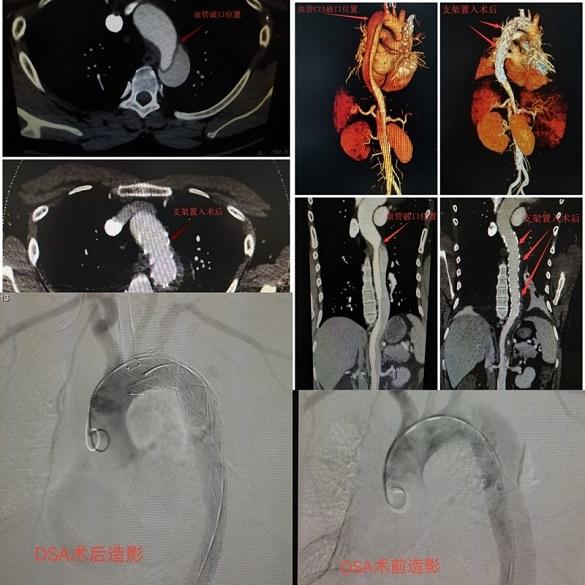

近日,一名中年男性突發(fā)劇烈胸背痛、伴暈厥、面色蒼白等狀況入我院急診科診治,經(jīng)胸腹主動(dòng)脈增強(qiáng) CT 提示,該患者診斷為 DeBakey III 型主動(dòng)脈夾層, 情況十分危急,隨時(shí)都會(huì)有生命危險(xiǎn),需立即手術(shù)與死神爭分奪秒搶救生命,在介入血管科主任周勇志及團(tuán)隊(duì)聯(lián)合麻醉手術(shù)部、導(dǎo)管室等多部門的通力合作下,耗時(shí)6小時(shí)成功在介入導(dǎo)管室完成這一列較為復(fù)雜的手術(shù),讓患者病情恢復(fù)穩(wěn)定,重獲新生。